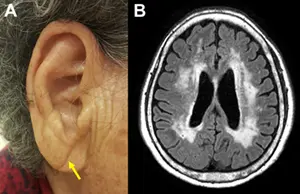

논문의 주요내용은 경도인지장애와 치매를 앓고 있는 환자들에게서 ‘대각선 귓불주름(Diagonal Earlobe Crease, 사진A)’이 정상인에서 보이는 것보다 높은 빈도로 관찰됐다는 것이다. 대각선 귓불주름은 노화와 연관된 신체 증후 가운데 하나로 알려져 있으나, 이는 모든 사람들에게 나타나는 것은 아니다.

정상인 243명과 인지장애가 있는 환자 (알츠하이머성, 혈관성) 471명에서 대각선 귓불주름을 관찰하여 다각도로 분석하였을 때, 인지장애 환자의 약 60%인 279명에서 대각선 귓불주름이 관찰됐다 (표1). 특히, 대각선 귓불주름의 존재 여부는 혈관성치매의 원인인 대뇌백질변성 (사진B)의 심한 정도와 알츠하이머치매의 원인인 베타-아밀로이드 양성률과 밀접한 상관관계를 보였다 (표2).